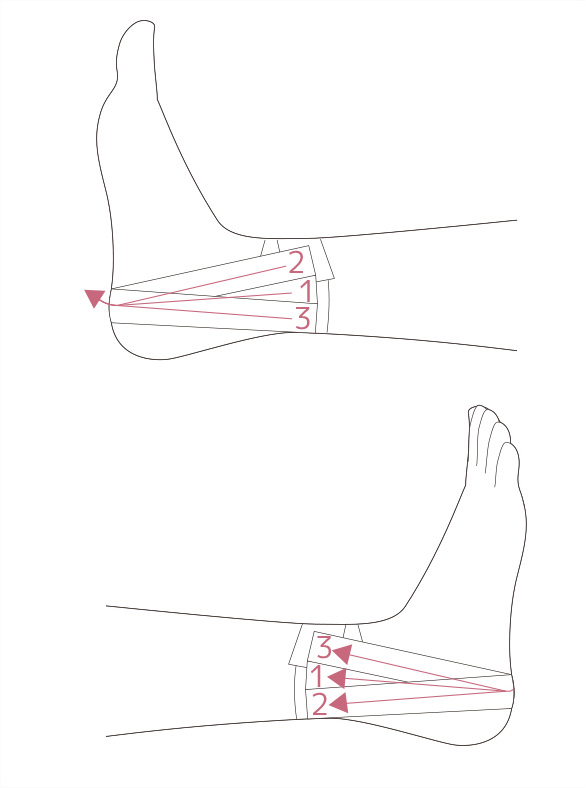

湿布の効果は何時間?短い時間でも効果はある?薬剤師が湿布 捻挫した場合にサポーターはいつまで着ける?その期間とは!? 足関節(足首)捻挫には湿布?アイシング?テーピング?捻挫 捻挫を早く治したいときは?捻挫の対処方法と処置の捻挫によくある症状 温感湿布と冷間湿布のどちらを使えばいいのか分からない 応急処置はどう対処したらいいのか知りたい 捻挫がクセになってしまいそうで不安 捻挫を未然に予防する方法を知っておその前に、説明を分かりやすく するために、 足首捻挫の分類から説明します。 足首を捻った(ひねった)方向による分類 一般的には大きく分けて、2つのタイプの捻挫があります。 一般的な捻挫の分類 1.内返し捻挫(内反強制) 足を内側に捻る 2.

足首 足首の内反捻挫 ねんざ 予防 動きやすさ優先編 テーピング 巻き方 バトルウィン

足首 足首の内反捻挫 ねんざ 予防 動きやすさ優先編 テーピング 巻き方 バトルウィン

最も基本的な足首捻挫予防のテーピング Vロック Mueller Japan